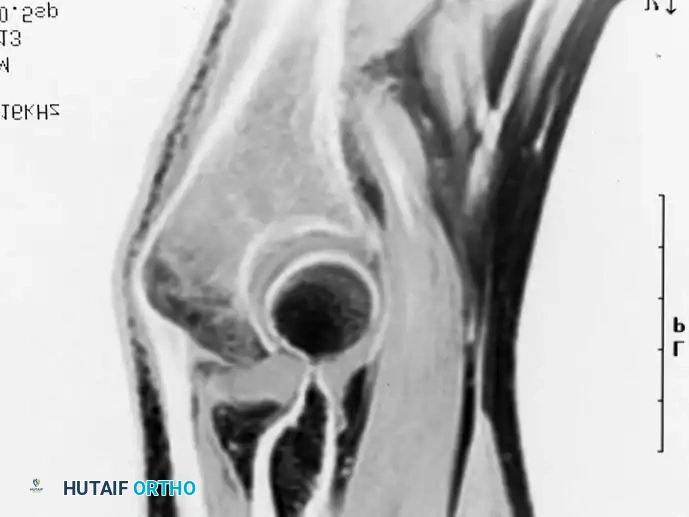

Distal Humerus and Elbow Reconstruction

When tumors involve the distal humerus, resection often requires sacrifice of the collateral ligaments and the articular surface of the elbow. Reconstruction is typically achieved using a linked, semi-constrained total elbow arthroplasty designed for oncologic defects.